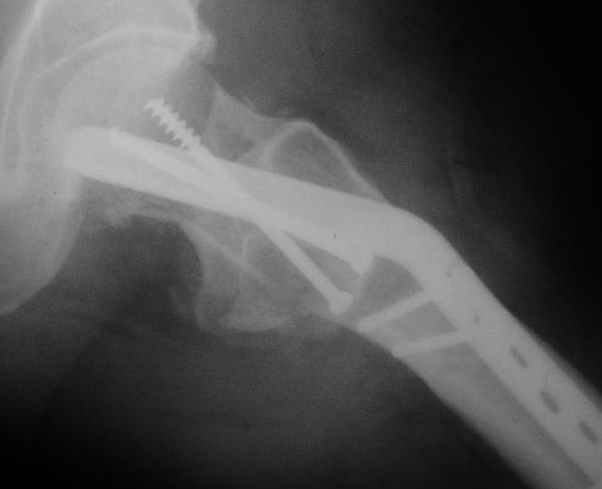

Мужчину 56 лет оперировали у нас в августе 2003 г. - вальгизируюшая остеотомия из-за позднего (через 2 мес. после травмы) поступления с переломом шейки бедра (картинки 1,2). Курильщик, соматической патологии не было. Сейчас поступил с жалобами на проблемы в области тазобедренного сустава, на снимках 3,4 видно вырезывание клинка.Чтоб можно посоветовать в этой ситуации? Заранее спасибо.

A male 56 years old was operated in Aug 2003 - valgus osteotomy performed because of delayed admission with neck fracture (2 months) images 1,2. Smoker, no other major medical problem. Now he re-admitted with the images 3,4.What would you do in the situation?THX in advance.

The osteotomy seems to be showing bony union. (New bone at the medial aspect). There is a big step in the union. The distal fragment is way out laterally.There is overiding of the neck over the head. The screws are out superiorly and the blade also coming out. There is no union of the neck fracture. The head does not seem to be normal- distorted in shape and probably starting of AVN too.

It will be a futile attempt now to get the neck fracture unite. The head has to come out and has to be replaced. Then comes the problem of the malaligned upper shaft. If it has united ( as what I think now) the union has to be undone and fragments aligned before introducing the stem.

If replacement is considered, the osteotomy has to be realigned as mentioned earlier.

Possible reasons why this happened: 1) There is not sufficient purchase of the screws into the head. In fact one can see some threads crossing the fracture site. This will prevent union across. Even the blade probably has less purchase. 2) After the osteotomy the distal fragment will have to be pushed more medially ( as we used to do McMurray's osteotomy 30 years ago) or abducted and fixed so the the fracture line becomes horizontal when the limb is brought to neutral.There is no abduction (so it is not a valgus osteotomy) and in fact the fragment is pulled out laterally. The fracture line has remained vertical and on weight bearing the shearing forces have pulled the implants superiorly. I am waiting for the answer from the replacement specialists.